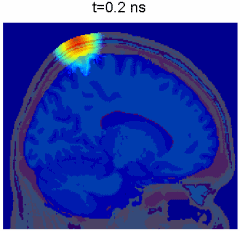

Monte Carlo simulation of photon propagation inside non-uniform tissue structures, has important applications in medical imaging, such as brain scans, but it is extremely computationally intensive.

Simulation of photon transport inside human brain - animation courtesy the researchers

Monte Carlo eXtreme, or MCX, is a Monte Carlo simulation software for time-resolved photon transport in 3D turbid media. It uses GPU based on massively parallel computing techniques and is extremely fast compared to the traditional single-threaded CPU-based simulations. Using an NVIDIA GTX 980 graphics card, the acceleration is about 300x-400x compared to a single thread on an Intel Core i7 4770k.